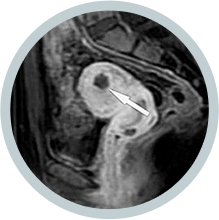

• 시술전 사진 시술 전

하이푸 시술 전에

MRI 조영증강영상에

점막하근종이 보임